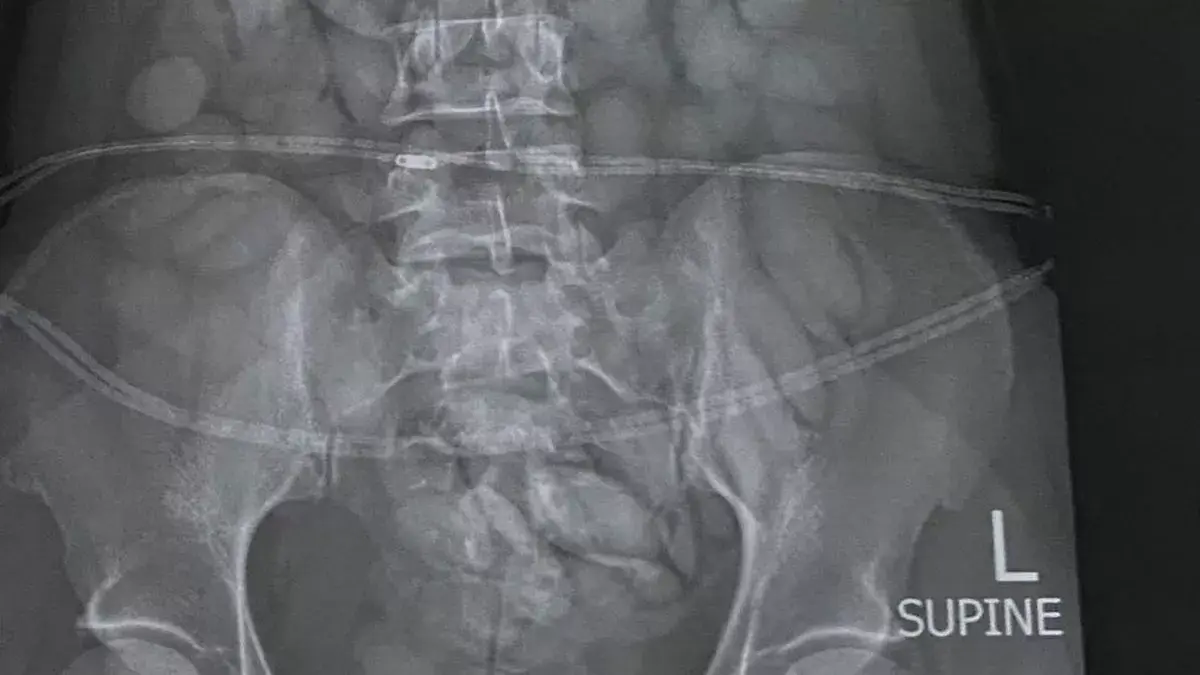

So, when the 30-year-old arrived, she was arrested and the X-ray instantly revealed everything they needed to know as it detected objects in her stomach.

Under police guard, she then ‘released’ 68 ‘bullets’ of suspected cocaine which South African Police racked in a total weight of about 850g.

Brig Athlenda Mathe, national police spokesperson, said: “The team immediately intercepted the drug mule as she was making her way through immigration. She was immediately arrested, taken to a local hospital where a medical X-ray confirmed and detected foreign objects in her stomach. She has already released more than 60 bullets of suspected cocaine thus far. She is currently under police guard and custody.”